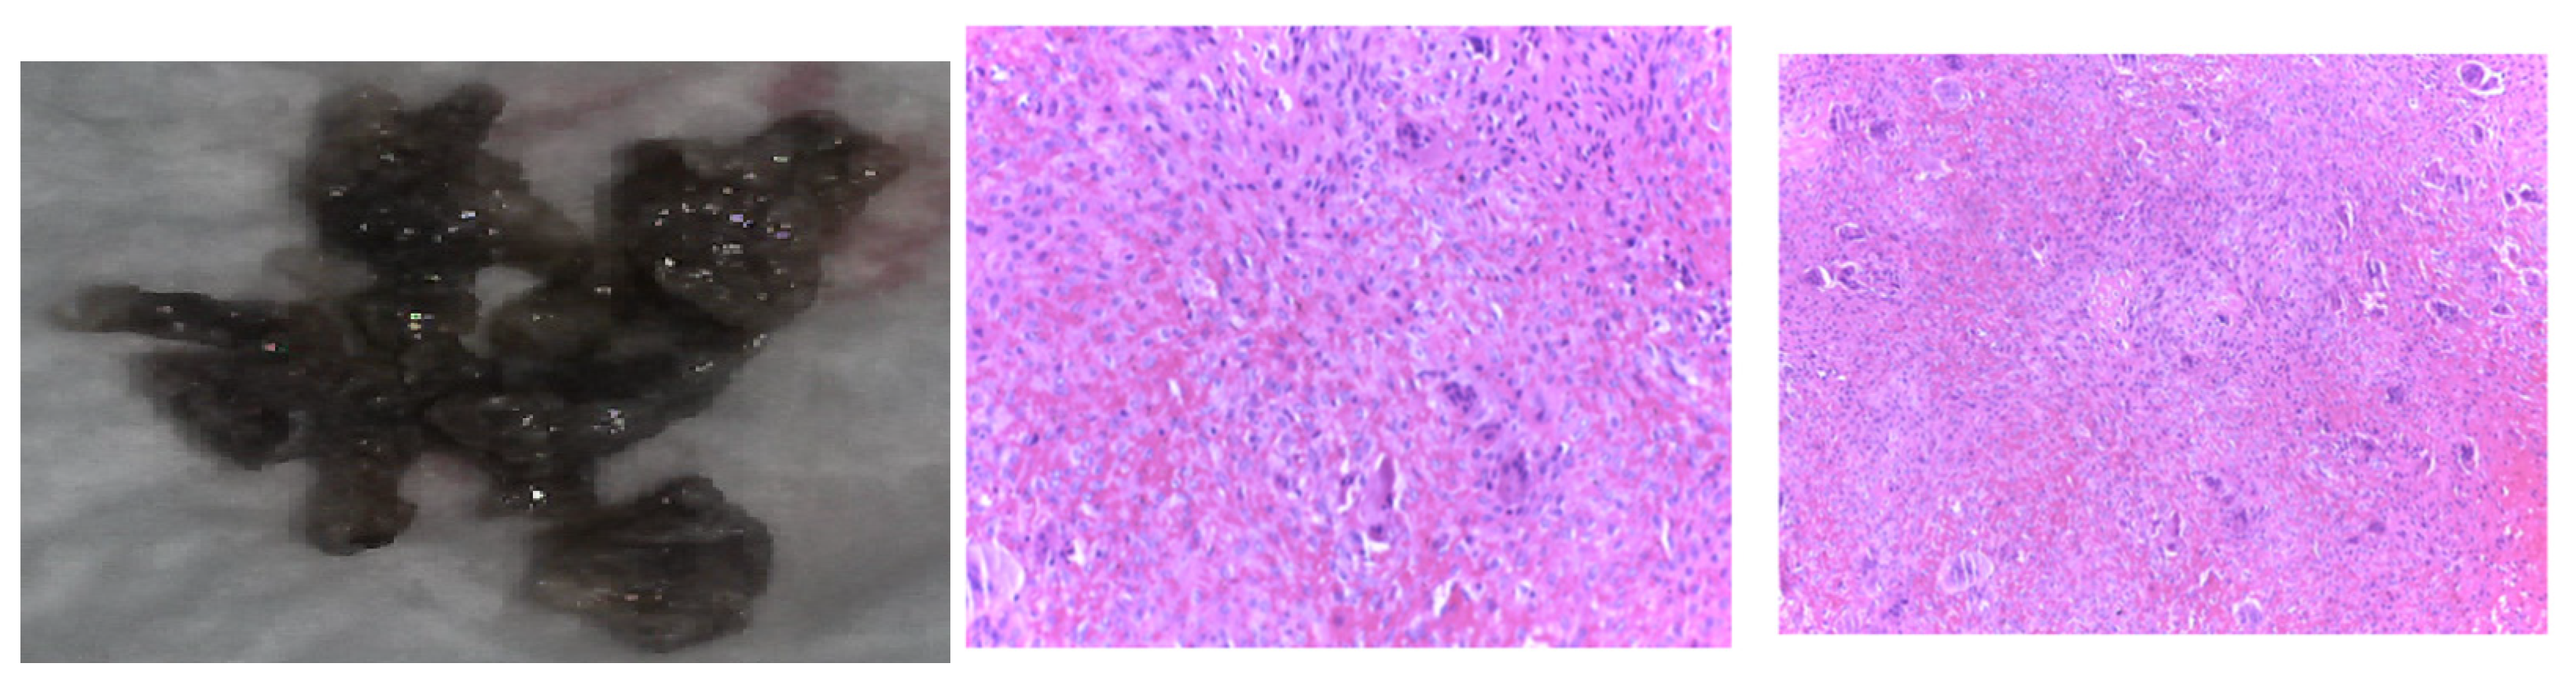

The multidisciplinary decision (also including a neurosurgical and neurological evaluation and assessment of the tumor-associated risks and the need for a clear distinction from oncologic traits) meant that a skull tumor lesion was enucleated. The histological report showed, at the macroscopic level, brown features with a crumbly consistency and an overall apparently well-vascularized tumor. The histological exam revealed osteoclast-like multinucleated giant cells arranged on a background of fusiform cells and focal fibrosis, diffuse hemorrhage, various fragments with short and thin cancellous bone lamellae with osteoblastic activity, and areas of multiple osteoclast-related bone lysis. These lesions were consistent with the diagnosis of a brown tumor of the bone, while a malignancy was ruled out (Figure 13).

Figure 13.

Brown tumor of the skull in chronic renal disease-related severe hyperparathyroidism: typical color features at the macroscopic level that stands for the tumor’s name (left); Both center and right subfigures are microscopic exams: hematoxylin-eosin (X10).